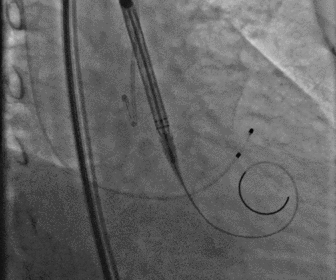

无鞘法上输送器

图片